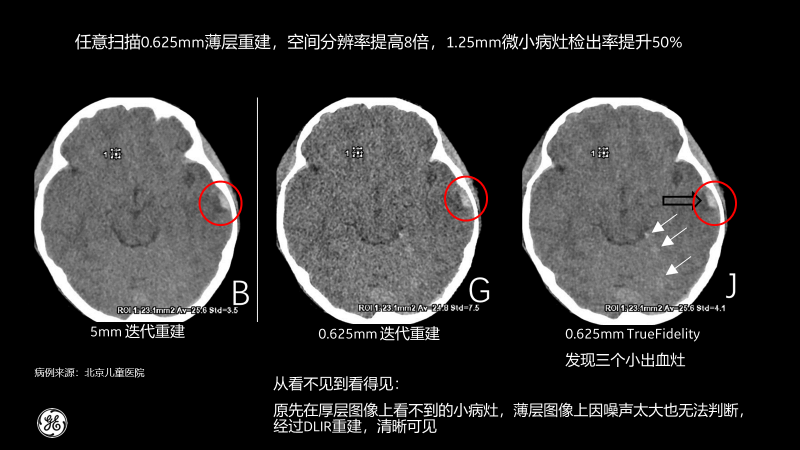

相比传统CT图像对腹部检查一般都选择5mm厚层重建,TrueFidelity可对任意体型任意部位的检查进行0.625mm的薄层图像重建,真实还原图像的解剖细节和纹理,提高微小病灶的发现几率,有助于早诊早治,极大提高医生的诊断信心。

北京儿童医院的测试病例也显示,经过TrueFidelity,任意扫描0.625mm薄层重建,空间分辨率能提高8倍,1.25mm微小病灶检出率提升50%,最终额外发现了3个之前看不到的微小病灶。